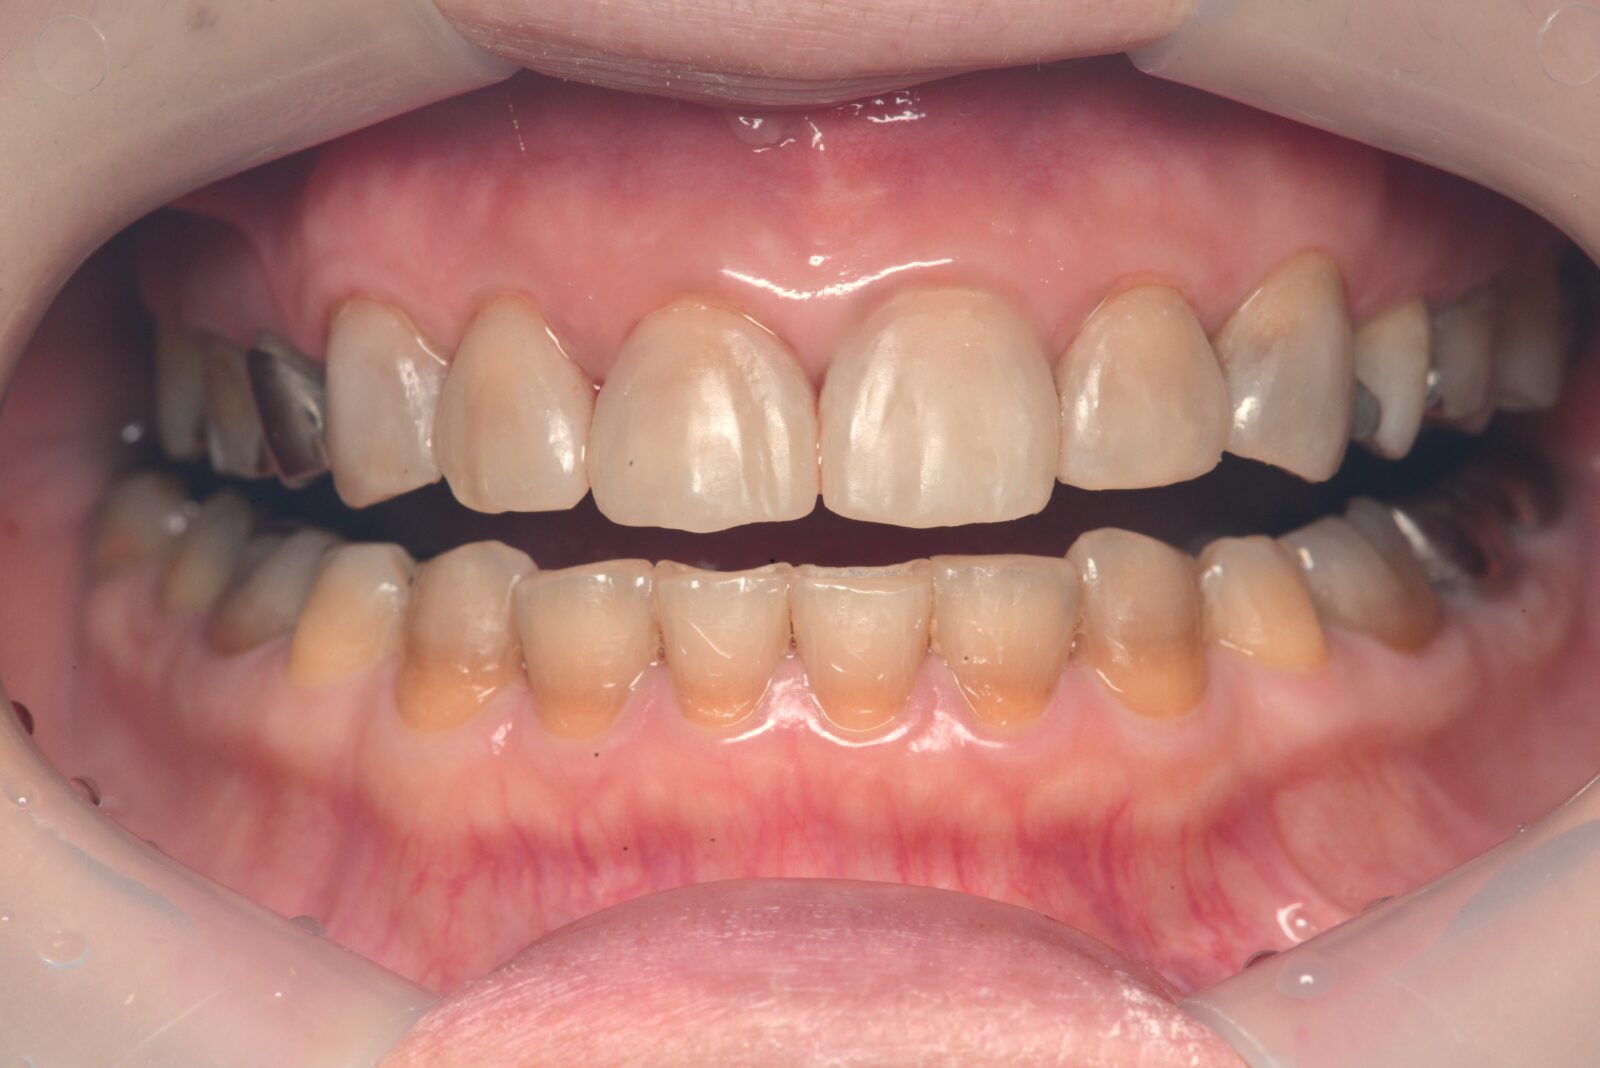

治療前 治療後

上顎前歯部ダイレクトボンディング

以前、他院で充填したコンポジットレジンの変色が気になるとのことで、上顎前歯部6本の充填のやり直し希望。 事前に、模型を作製し、予測完成状態を確認していただき、了承を得たため、治療開始。 ラバーダム下で、旧充填物と虫歯を除去し、自費コンポジットレジンを使用し充填。表面のコーティングと研磨を…